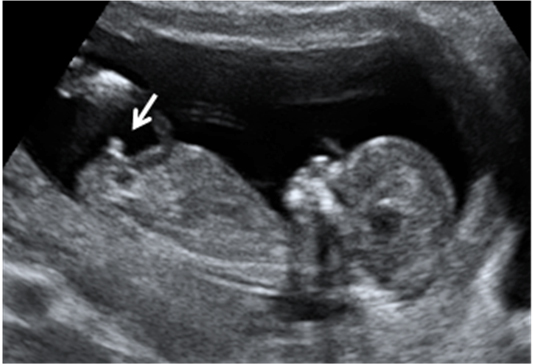

Ecografía 4D semana 11: Siameses unidos por el abdomen

La ecografía en 4D (vídeo) no deja lugar a dudas. Se trata de un embarazo de siameses de 11 semanas de gestación, que están unidos por la zona abdominal, ya que comparten una pequeña parte de hígado. La movilidad de los bebés es reducida, como vemos en las imágenes, debido a la unión de sus cuerpos. Uno de los hermanos (el de la derecha) mueve la cabeza hacia atrás, mientras las piernas se entrecruzan. Los especialistas siguen este tipo gestaciones muy de cerca y valoran la separación quirúrgica de los bebés, una vez que se produce el parto.